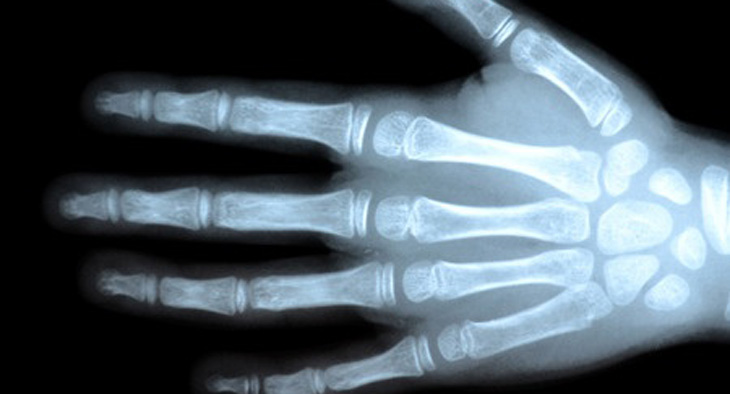

5. Vocabulary: Parts of the body.

Match the words to the numbers. Listen and repeat the words.

Now listen again and repeat the words.